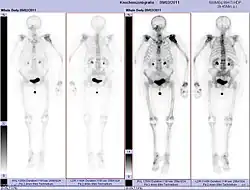

- Vues de fractures pathologiques

Scintigraphie corps entier avec 99mTc-HDP de la patiente avec une fracture du bras due à une métastase du cancer du sein